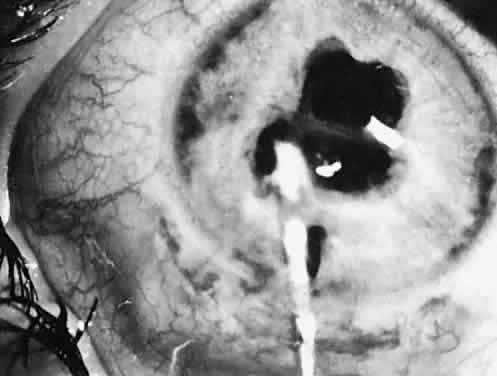

Eyes with pediatric cataracts appear to have an abnormal outflow facility and a propensity for open-angle glaucoma. Simon and colleagues52 reported glaucoma in 24% of eyes treated for cataracts and followed for at least 5 years. Johnson and Keech53 reported glaucoma in 32% of patients with PHPV-type cataracts (eight of 25) and the same 32% in patients with infantile cataract (15 of 47). The mean time of onset of glaucoma was 65 months and 47 months after surgery, respectively. Chrousos and associates38 found chronic glaucoma in 6.1% of treated eyes. Eyes with rubella, uveitis, or microphthalmia are particularly affected. A slightly more anteriorly placed incision and careful wound closure prevent iris-to-cornea adhesions. Figure 31 shows a gonioscopic view of an angle of a 5-year-old child in whom late-onset glaucoma developed after cataract surgery. Walton51 has described a near-constant (96%) but variable angle defect characterized by blockage of the trabecular meshwork by an acquired repositioning of the iris against the posterior trabecular meshwork.

Fig. 31. An open filtration angle with a three-mirror pediatric Goldmann lens in a 5-year-old child. Glaucoma developed in this patient after cataract surgery.